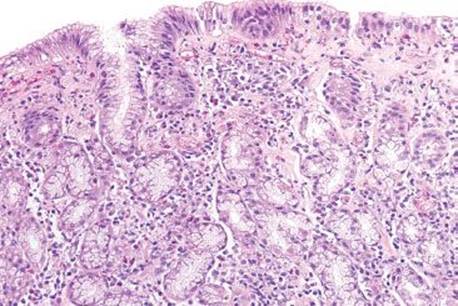

Figure 2.144 Collagenous gastritis pattern, olmesartan. This antrum biopsy shows intraepithelial lymphocytosis and a markedly abnormal subepithelial collagen table. The pink band is seen right beneath the surface epithelium and the lamina propria contains increased chronic inflammation. This patient was taking olmesartan, an antihypertensive drug known to cause collagenous gastritis and sprue-like enteropathy.